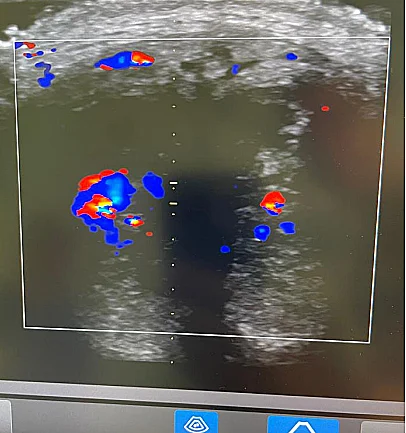

למרות האתגרים הרבים שנבעו מהזיהום, הניתוח הוכתר כהצלחה. חלקית. הרופאים הצליחו להציל את קצה הפין וכשני סנטימטרים בלבד. שאר החלקים היו פגומים מכדי להצילם.